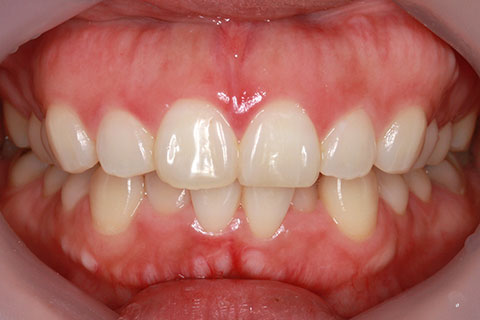

フルリンガル矯正1(上下の歯を舌側矯正で治療)

治療前

治療中

治療後

- 年齢・性別

- 33歳女性

- 治療期間

- 2年0ヶ月

- 抜歯

- 上顎4番抜歯。下顎5番欠損。

- 治療費

- 120万円(税込み)

- 備考

- フルリンガル矯正

- 治療内容

- 上顎前歯の叢生改善および下顎前歯の空隙閉鎖

- 施術の副作用(リスク)

- 装置が裏側について、目視ができないため、しっかりとブラッシングができているかどうかわかりにくい。